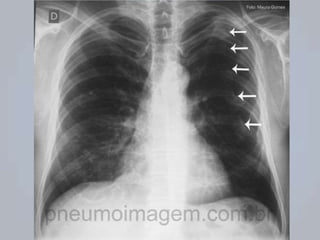

PNEUMOTÓRAX SIMPLES

 Ar no espaço pleural ( ar  colabamento);

 AVALIAÇÃO: dor torácica e sinais de disfunção

respiratória.

 EXAME FÍSICO:  M.V. - Timpanismo na percussão.

 TRATAMENTO:

 O2 suplementar;

 Acesso IV (caso CHOQUE);

 Oximetria de pulso e capnografia;

 Decúbito semissentado (conforto);

 Transporte rápido;

 Tratamento precoce (Simples  Hipertensivo).